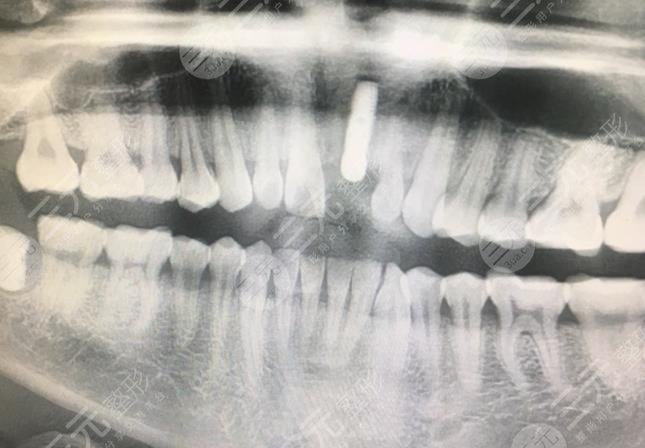

Once I was playing with a friend, I accidentally fell and knocked out my front teeth, and I was very uncomfortable when I looked at it, so I came to Shanghai Yida Dental Clinic to do dental implant projects here, because I had learned about this before, so the process of this interview and examination was relatively smooth, and the doctor also explained to me a lot of dental implant project related content, but because I broke my front teeth, so it is a little difficult to implant it. However, the latter result is still relatively good.

Because the treatment cycle of dental implants is relatively long, first the implant is implanted, and then the implant and the tooth bone are fused, I waited for almost 3 months before going to the hospital for the installation of the abutment and crown, and after the crown is in order, the whole dental implant is almost done. The end result is that my teeth are much sharper and much harder than before.